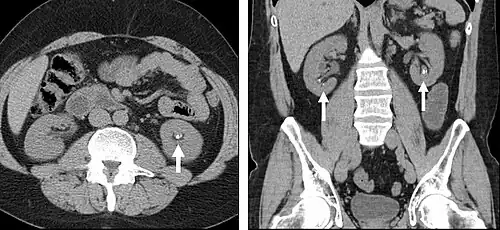

The most common technique is to perform portal venous phase imaging in the abdomen and pelvis (approximately 60–90 seconds after contrast administration, figure 2). This results in near optimal contrast opacification of the majority of the solid abdominal organs and it is used for a wide variety of indications: nonspecific abdominal pain; hernia; infection; masses (with a few exceptions such as hypervascular, renal, and some hepatic tumors); and in most follow-up examinations. As a general rule, this single phase is adequate unless there is a specific clinical indication that has been shown to benefit from other phases.

FIGURE 2. Contrast enhanced CT demonstrating parenchymal enhancement of the intra-abdominal organs in the portal venous phase (axial left, coronal reformat right).